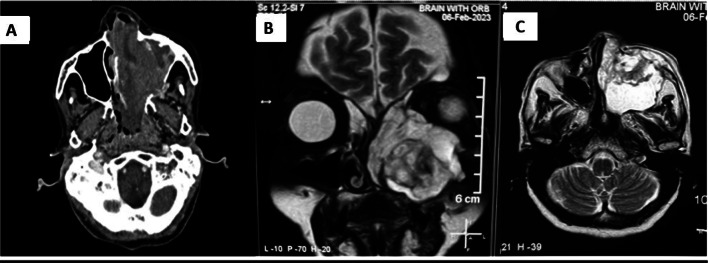

Contrast-enhanced CT and MRI of the nose, paranasal sinus, and orbit (Fig. 1) revealed a heterogeneously enhancing soft tissue density occupying the left maxillary sinus and nasal cavity extending up to the nasopharynx, with erosion of the medial, anterior, and posterior lateral walls of the maxilla (Fig. 2a) with extension into left infratemporal fossa and pterygopalatine fossa. There was involvement of Ethmoid and Sphenoid sinuses. The septum was eroded, and extension into the right nasal cavity was noted. We suspected malignancy and did all the metastatic workup. The patient underwent a biopsy with subsequent histopathological examination revealing a fibrous tissue with cellular infiltrated rich in eosinophils(Fig. 2A), the evaluation of markers revealed positivity for CD-68 (Fig. 2B), CD-1a (Fig. 2C) and S-100 (Fig. 2D) suggestive of Langerhans Cell Histiocytosis (LCH). To further evaluate the generalized bony involvement, plain radiography of the chest, skull, and limbs was done, and no abnormality was detected. Endocrinological evaluation was normal.

Fig. 1.

Radiological images.

A Contrast CT showing heterogeneously enhancing soft tissue density in left maxillary sinus and left nasal cavity. B MRI T2 weighted image Coronal view showing hyperintense lesion in left maxillary sinus with erosion of roof and medial wall. C MRI T2 weighted image axial view showing lesion eroding anterior and posterolateral wall of maxillary sinus